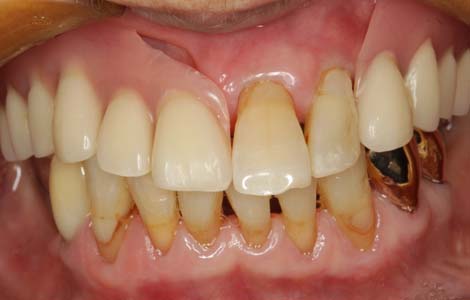

すれ違いはインプラント

入れ歯を外した時に、上下の歯が1箇所も噛み合わない状態を、「すれ違い咬合」と呼びます。この様な状態の方に入れ歯を作っても、噛むたびに歯がない方が大きく沈み込んしまうため、入れ歯ががたつき満足してもらえることはありません。この症例では、下の入れ歯を何度作っても痛くて噛めないという訴えでした。右下に傷がありました。

インプラントで入れ歯の沈みこみを抑える

解決策は、歯を抜いて総入れ歯にすることで入れ歯の沈みこみを均等にするか、インプラントを入れて入れ歯の沈みこみを抑えるようにするしかありません。この症例では右下に2本のインプラントを入れました。これで右下の入れ歯の沈みこみが防げるようになったので、痛みもなくお食事ができるようになりました。